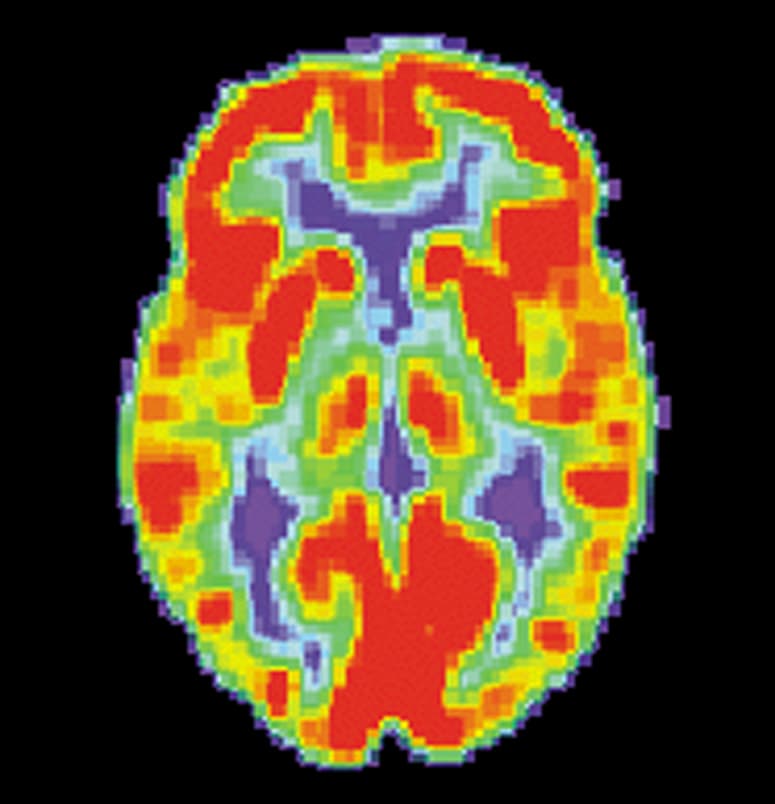

Brain positron emission tomography